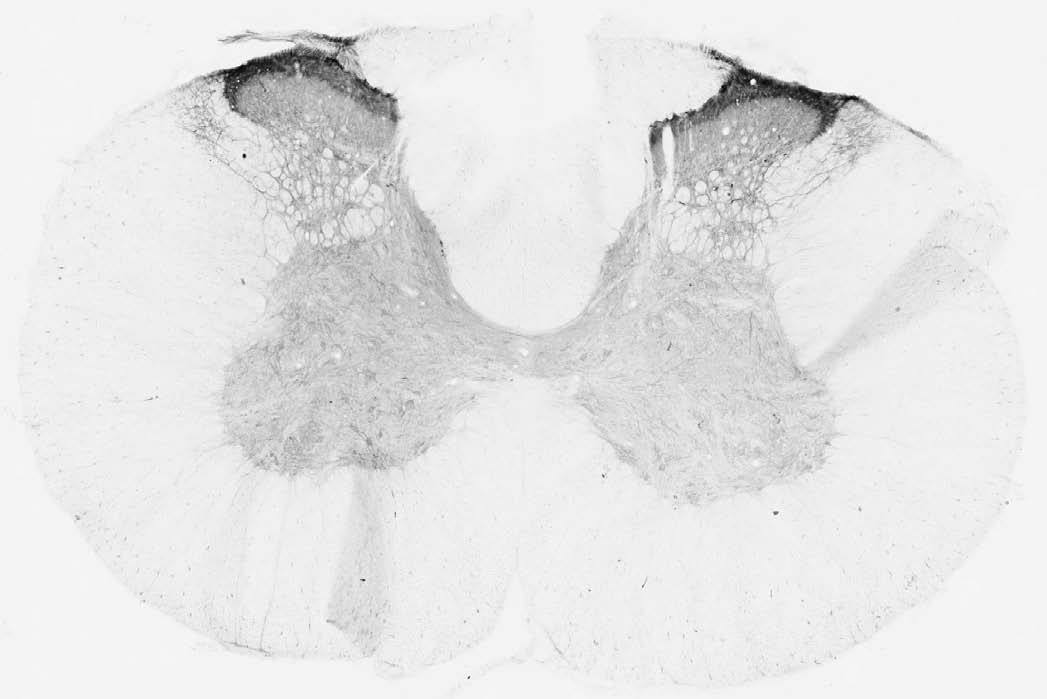

Supportive validation

- Submitted by

- Antibodies Incorporated / NeuroMab (provider)

- Main image

- Experimental details

- Adult rat spinal cord immunohistochemistry.